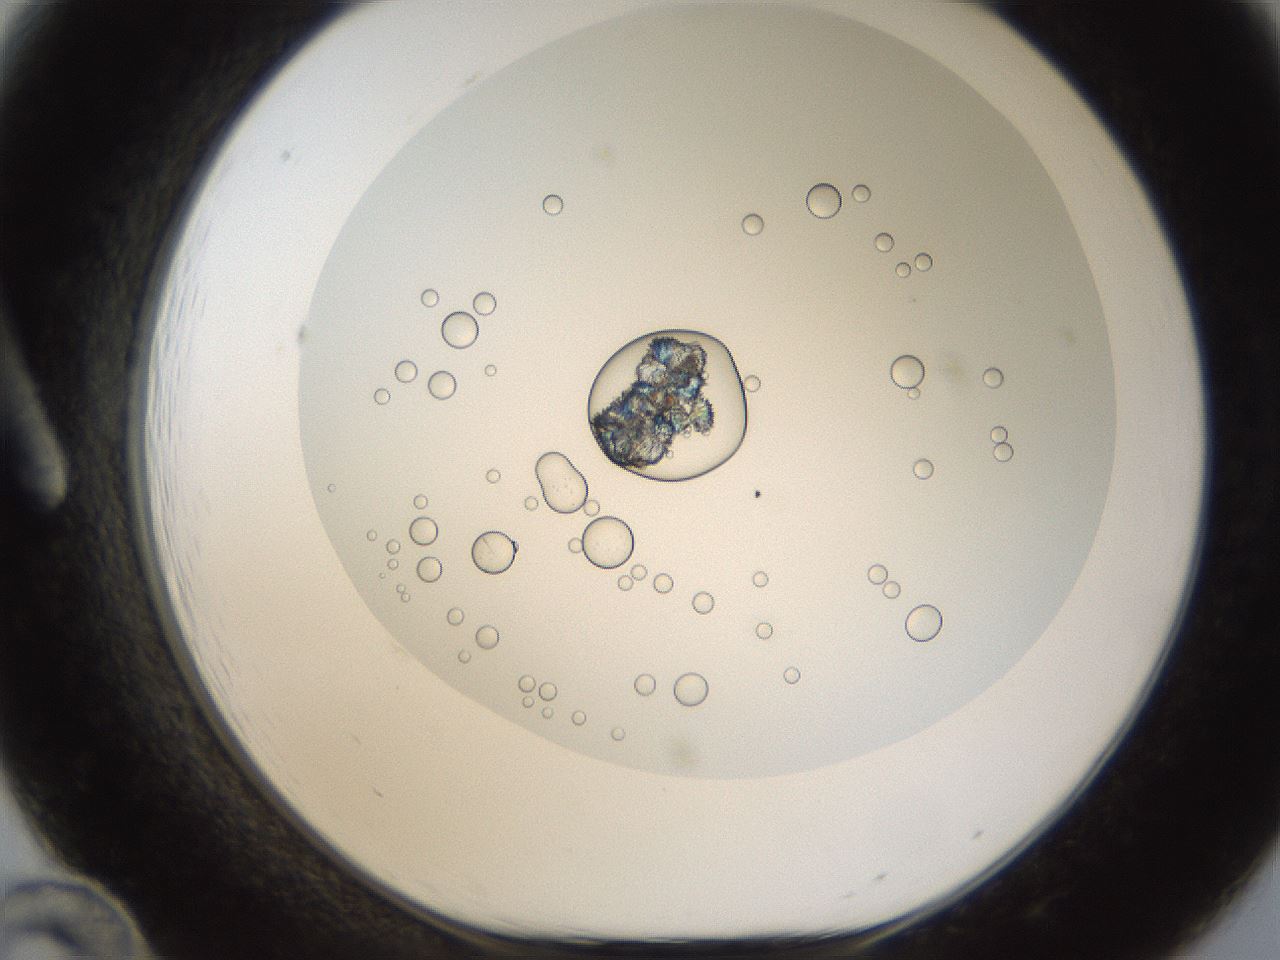

folderID213_plateID1213_batchID3626_wellNum12_profileID1_d1_r68982_ef.jpg